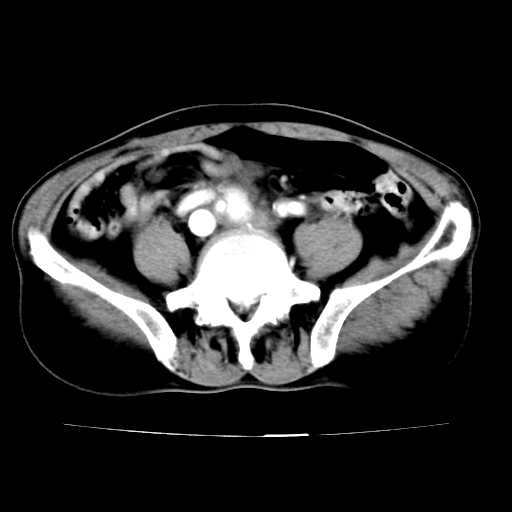

男,75岁,腹痛月余,彩超发现脐周腹主动脉异常回声。临床诊断:腹主动脉瘤。

ct诊断:右骼总动脉囊性动脉瘤并瘤内附壁血栓形成,与下腔静脉之间形成动静脉瘘。

请问各位老师:能排除动脉瘤破裂的可能吗?

各位老师注意到下腔静脉的充盈缺损了吗?注意到动静脉漏了吗?

当时是扫描的标准动脉期,可是下腔静脉与腹主动脉同步强化且幅度一致。所以我想动静脉瘘是存在的。